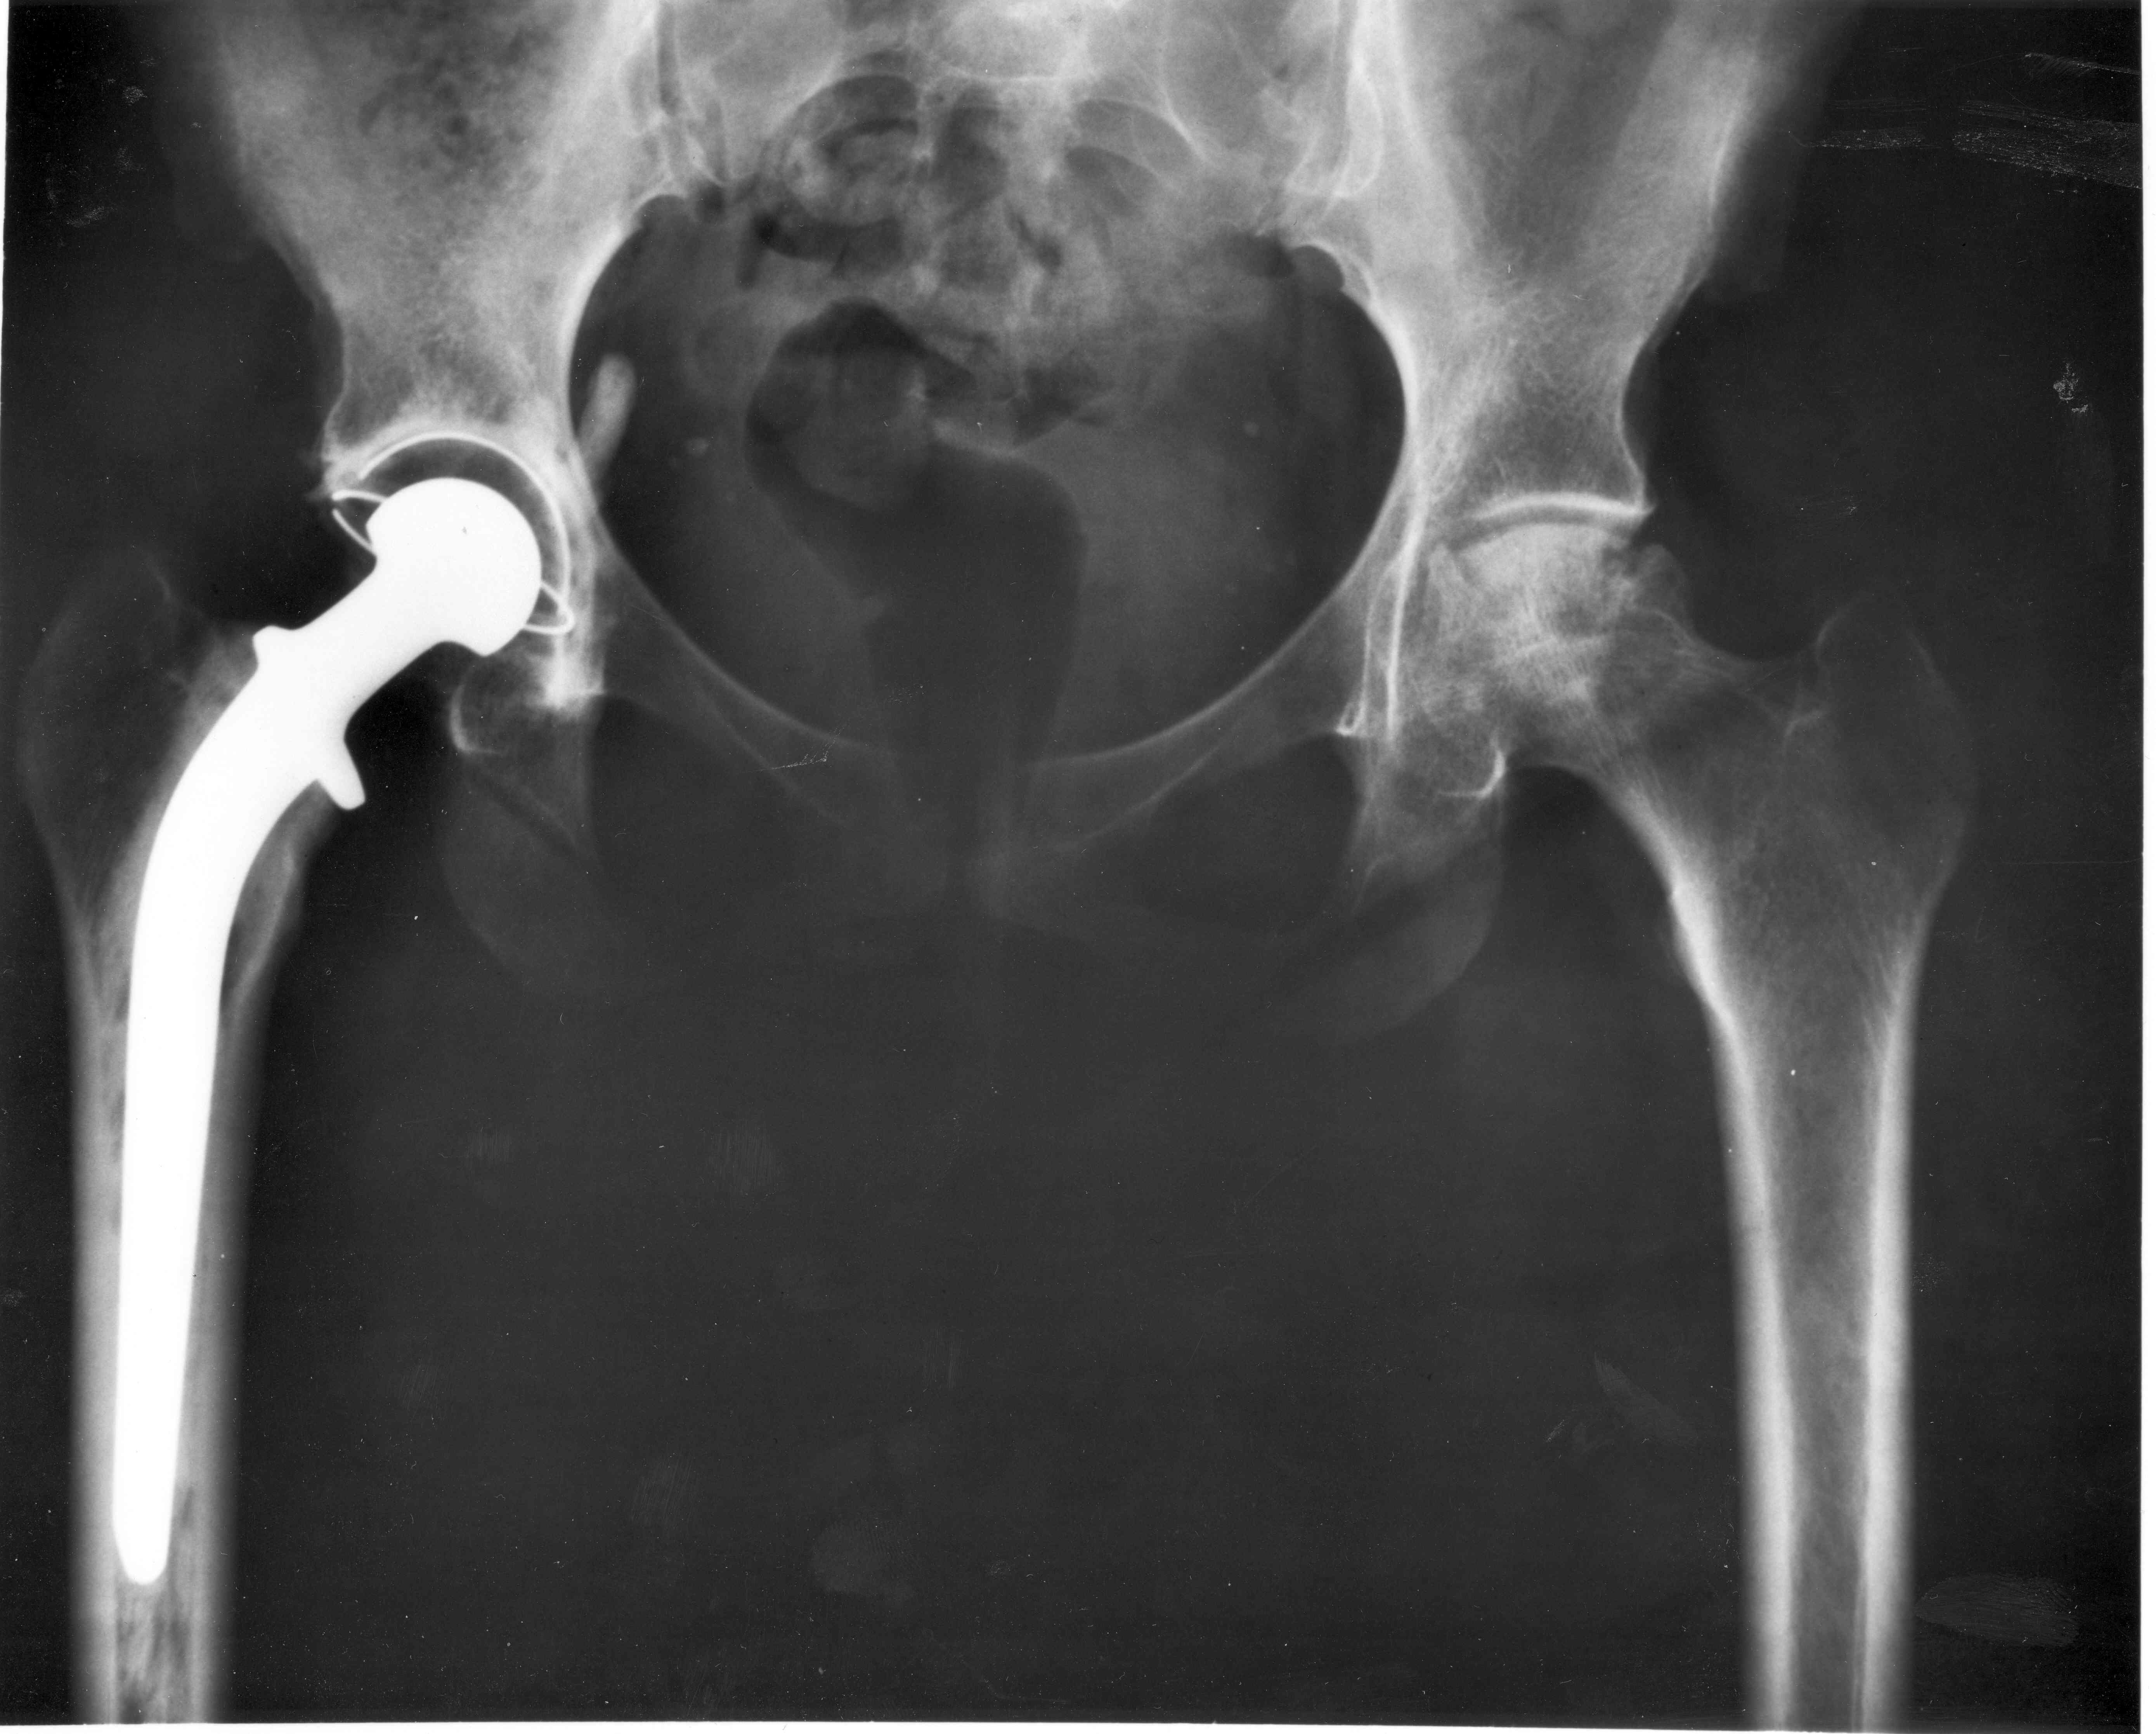

2. 멈춰버린 걸음을 다시 뛰게 하다: 인공 고관절(Artificial Hip Joint)

인공와우가 감각의 혁명을 이끌었다면, 비슷한 시기 영국에서는 움직임의 혁명이 일어나고 있었습니다.

바로 '인공 고관절'의 등장입니다.

오래전부터 상아나 유리 등으로 손상된 엉덩이 관절(고관절)을 대체하려는 시도는 있었지만, 번번이 실패로 돌아갔습니다.

진짜 성공의 문을 연 사람은 영국의 정형외과 의사, '존 찬리(Sir John Charnley)' 경입니다.

그는 1960년대 초, 마찰을 획기적으로 줄인 새로운 디자인을 고안했습니다. 단단한 금속으로 만든 대퇴골두(허벅지뼈 머리)와 특수 플라스틱(폴리에틸렌)으로 만든 비구컵(골반 소켓)을 조합하고, '골 시멘트'라는 접착제를 사용해 뼈에 단단히 고정하는 방식이었죠.

이 '저마찰 인공 고관절'은 이전의 어떤 시도보다 월등히 뛰어난 성능과 수명을 자랑했습니다. 존 찬리 경의 수술을 받은 환자들은 지긋지긋한 통증에서 벗어나 다시 자유롭게 걷고 움직일 수 있었습니다. 그의 수술법은 현대 인공관절 수술의 기초가 되었고, 지금도 전 세계 수많은 환자에게 제2의 삶을 선물하고 있습니다.

(이미지 삽입: 구글 이미지 검색 키워드 - 'Sir John Charnley hip replacement', 'early artificial hip joint')